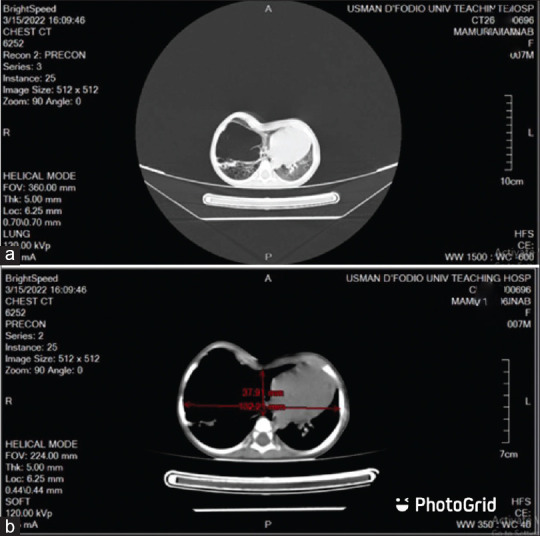

摘要:先天性肺囊性腺瘤畸形和严重的鸡胸(PE)并存是一种不常见的表现,给治疗带来了巨大挑战。传统的处理方法是分期处理,但越来越多的报告显示,采用微创技术(视频辅助胸腔镜手术 [VATS] 和 PE 微创修复术 [MIRPE])同时进行单期修复的疗效更佳。在我们的搜索范围内,以前还没有关于对两种异常情况进行单阶段开放式修复的报道。我们报告了对一名 9 个月大的同时患有这两种畸形的婴儿进行开放性肺叶切除术和改良 Ravitch 手术的成功单阶段治疗。我们的目的是报告使用开放式技术同时对两种畸形进行单阶段修复的可行性和安全性,因为在我们的环境中还无法使用 VATS 和 MIRPE。

Abstract: Coexisting congenital cystic adenomatous malformation of the lungs and severe pectus excavatum (PE) is an uncommon presentation that poses significant management challenges. Conventionally managed in a staged manner, there are increasing reports of superior outcomes with single-staged concurrent repair with minimally invasive techniques (video-assisted thoracoscopic surgery [VATS] and minimally invasive repair of PE [MIRPE]). The outcome of a single-stage open repair for both anomalies has not been previously reported to the best of our search. We report the successful single-stage management of a 9-month-old infant with both anomalies who had an open lobectomy and modified Ravitch procedure. We aim to report the feasibility and safety of a single-stage concurrent repair of both conditions using open techniques, as VATS and MIRPE are not readily available in our environment.